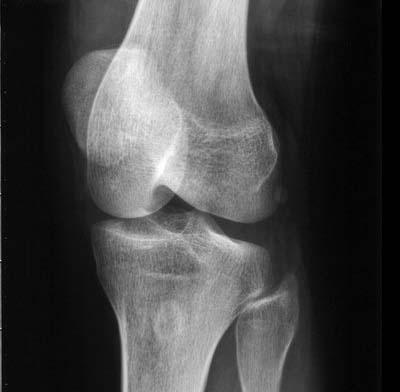

(图:患者左膝关节疼痛,局部红肿)

体检:膝关节肿胀,皮温高,行动不利。双膝关节疼痛,尤以左膝关节痛重。

CT片示:左膝关节软组织肿胀,关节未见变形。